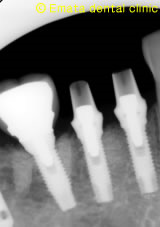

外側骨がないのがわかります。

GBR(骨造成をおこないました)

レントゲンでもインプラントのまわりの骨も安定しています。